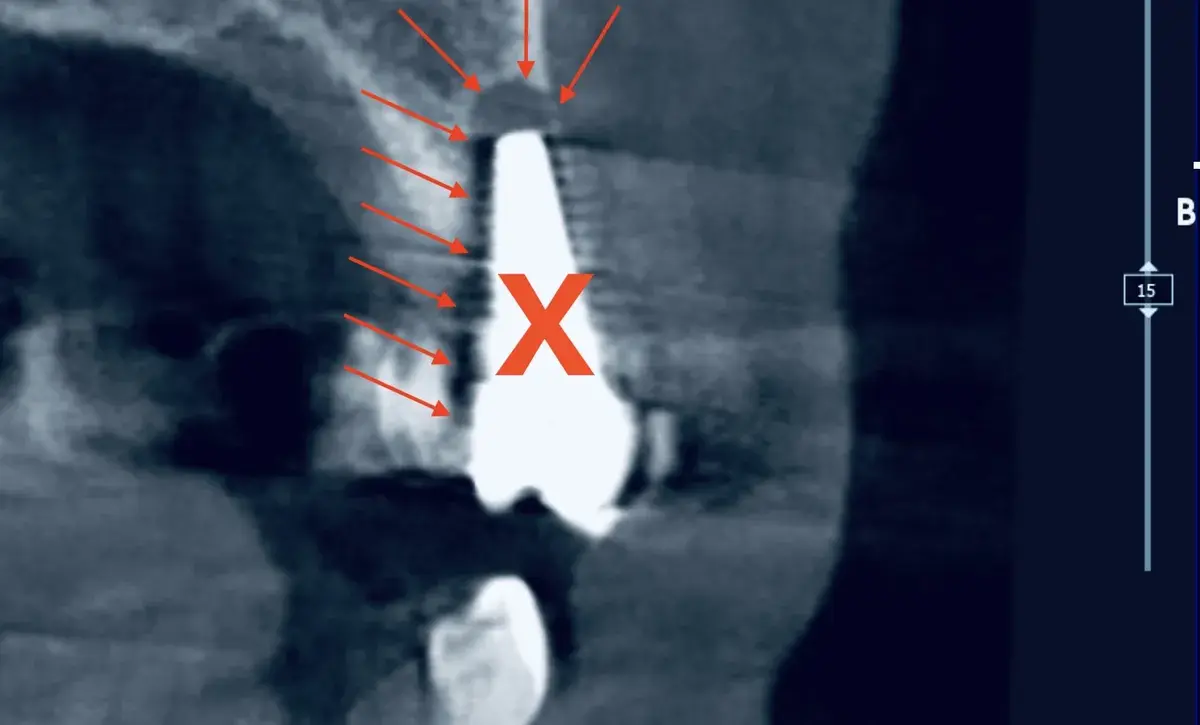

Somiglianze, differenze e meccanismi patogeni tra il microbiota della peri-implantite e quello della parodontite. Una rassegna della letteratura.